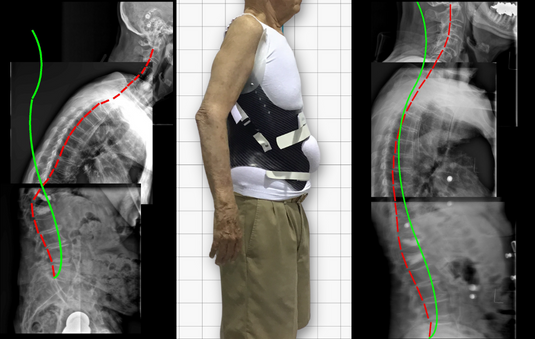

KyphoBrace: A specific brace for treating hyperkyphosis, Scheuermann’s kyphosis and poor posture.

KyphoBrace™ is a type of ScoliBrace specifically designed for hyperkyphosis in adolescents and adults. It is an evidence-based, non-surgical treatment option only available through ScoliCare clinics and certified ScoliBrace Providers.

The corrective approach aims to restore a patient’s thoracic kyphosis angle to within a range that is considered normal for their age. Curve reduction is often achieved while improving the patient’s posture and overall appearance of their body.